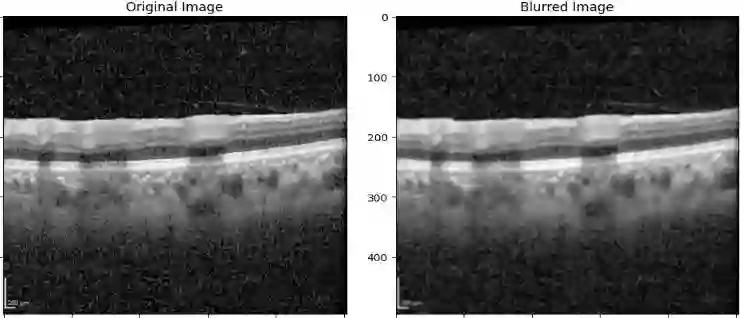

Ophthalmic diseases represent a significant global health issue, necessitating the use of advanced precise diagnostic tools. Optical Coherence Tomography (OCT) imagery which offers high-resolution cross-sectional images of the retina has become a pivotal imaging modality in ophthalmology. Traditionally physicians have manually detected various diseases and biomarkers from such diagnostic imagery. In recent times, deep learning techniques have been extensively used for medical diagnostic tasks enabling fast and precise diagnosis. This paper presents a novel approach for ophthalmic biomarker detection using an ensemble of Convolutional Neural Network (CNN) and Vision Transformer. While CNNs are good for feature extraction within the local context of the image, transformers are known for their ability to extract features from the global context of the image. Using an ensemble of both techniques allows us to harness the best of both worlds. Our method has been implemented on the OLIVES dataset to detect 6 major biomarkers from the OCT images and shows significant improvement of the macro averaged F1 score on the dataset.